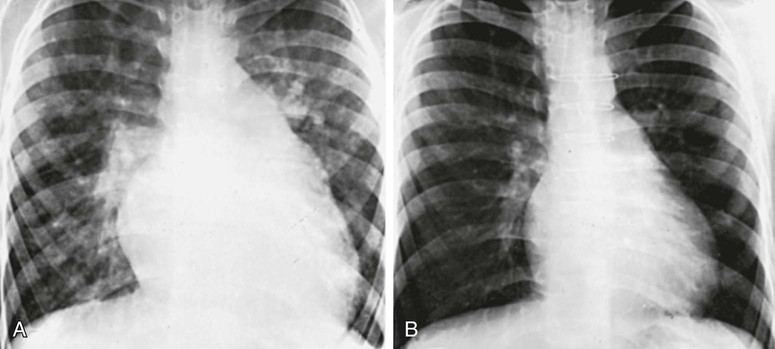

In patients with small VSDs, the chest x-ray is usually normal, although minimal cardiomegaly and a borderline increase in pulmonary vasculature may be observed. The electrocardiogram is generally normal but may suggest left ventricular hypertrophy. The presence of right ventricular hypertrophy is a warning that the defect is not small and that the patient has pulmonary hypertension or an associated lesion such as pulmonic stenosis. In large VSDs, the chest x-ray shows gross cardiomegaly with prominence of both ventricles, the left atrium, and the pulmonary artery (Fig. 426-8). Pulmonary vascular markings are increased, and frank pulmonary edema, including pleural effusions, may be present. The electrocardiogram shows biventricular hypertrophy; P waves may be notched or peaked.

After surgical obliteration of the left-to-right shunt, the hyperdynamic heart becomes quiet, cardiac size decreases toward normal (see Fig. 426-8), thrills and murmurs are abolished, and pulmonary artery hypertension regresses. The patient's clinical status improves markedly. Most infants begin to thrive, and cardiac medications are no longer required. Catch-up growth occurs in most patients within the next 1-2 yr. In some instances after successful surgery, systolic ejection murmurs of low intensity persist for months. The long-term prognosis after surgery is excellent. Patients with a small VSD and those who have undergone surgical closure without residua are considered to be at standard risk for health and life insurance.